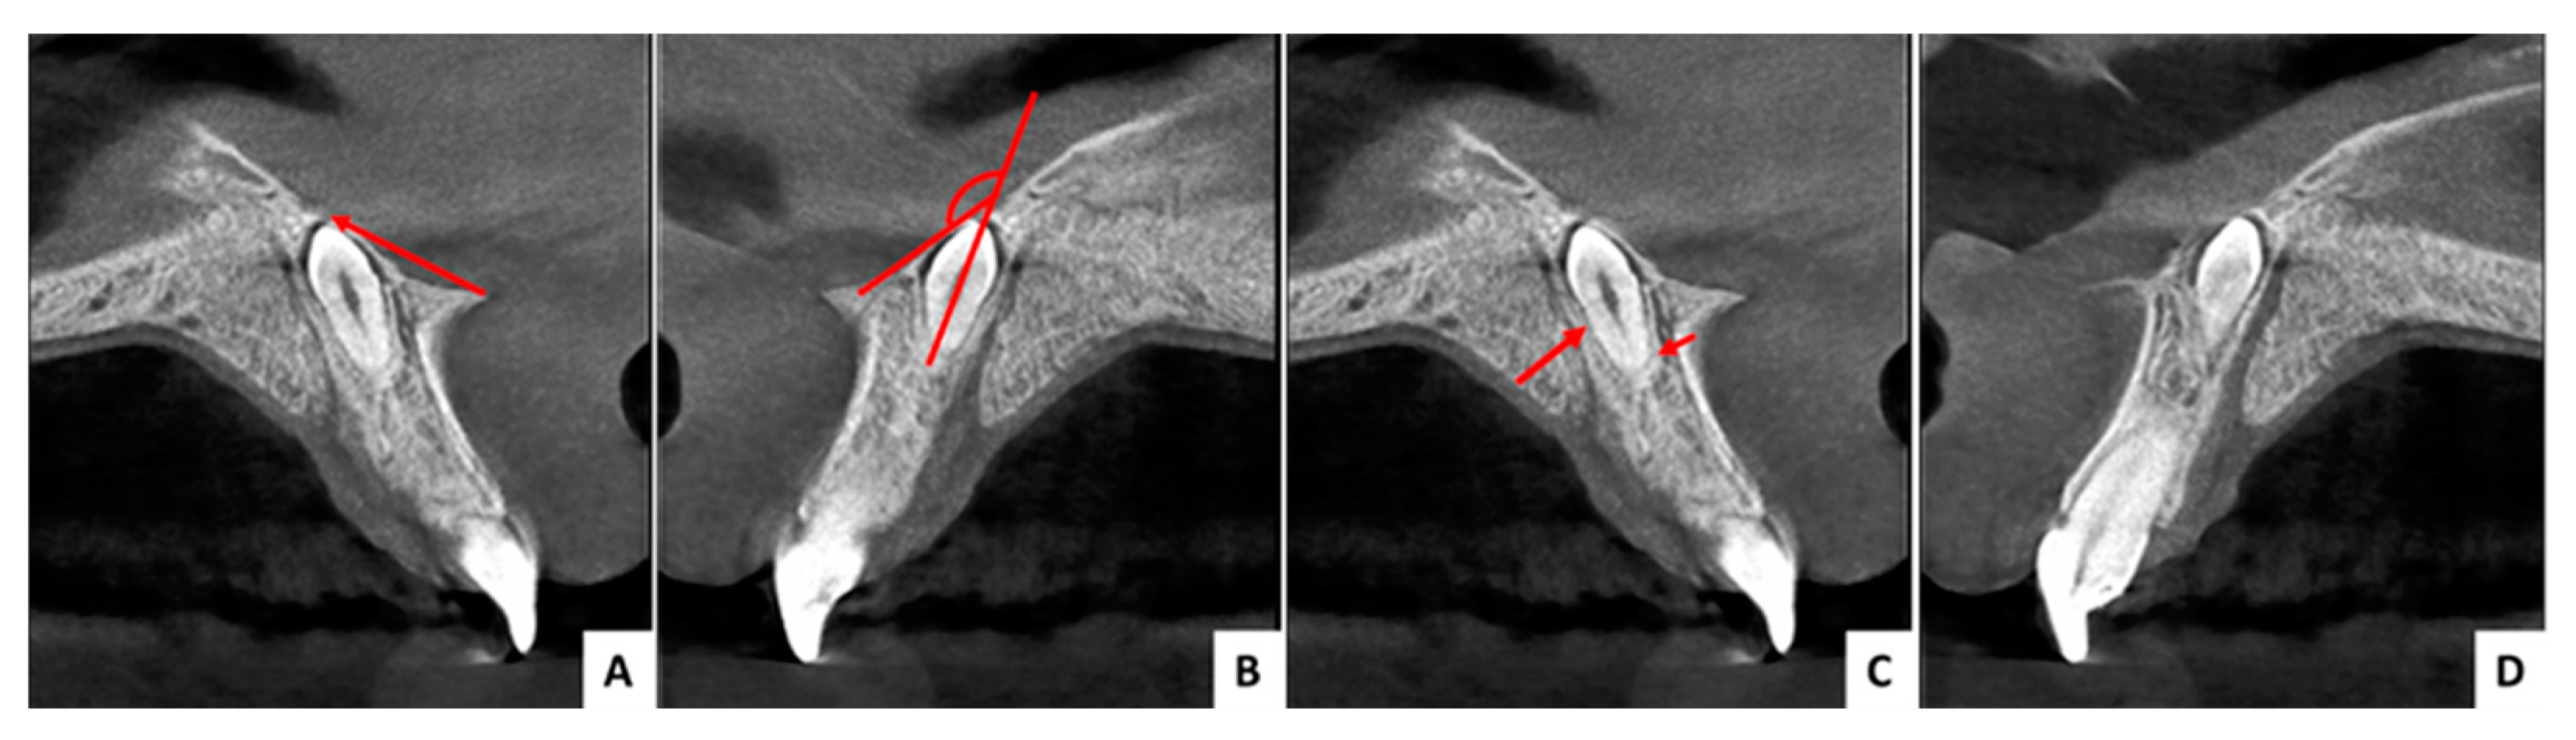

3.1. Case 1 (Figure 3, Figure 4 and Figure 5)

3.2. Case 2 (Figure 6, Figure 7 and Figure 8)

3.3. Case 3 (Figure 9, Figure 10 and Figure 11)

| Angle formed by the mesiodens axis with the nasal floor | 85.93° | 143.5° | 144.4° |

| Distance from the ANS (mm) | 8.98 | 8.11 | 13.22 |

| Distance to mesiodens from buccal aspect (mm) | 4.71 | 3.70 | 3.84 |

| Distance to mesiodens from palatal aspect (mm) | 6.43 | 5.47 | 6.82 |

| Relation with nasal cavity | Covered with bone | Submucosally | Covered with bone |

| Position regarding nasopalatine canal | In front | In front | In front |